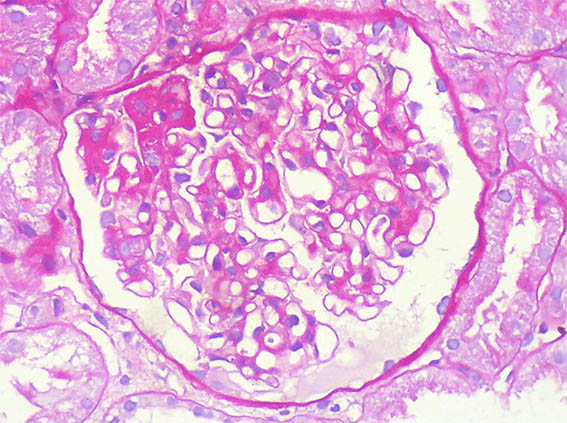

A 25-year-old woman with no relevant history is evaluated for presenting 3 months of evolution of constitutional symptoms, disseminated skin lesions with vasculitis-like appearance, polyarthritis affecting small and medium joints, anemia, acute phase reactants elevation, lymphopenia, hypocomplementemia C3 and C4, uroanalysis with active sediment and subnephrotic proteinuria: 1.8 g/24h; Cr; 1.1 mg/dL, BUN: 18 mg/dL. ANAs and anti-DNA positive at high titers, anti-RNP positive, VDRL falsely positive. Anticardiolipin and lupus anticoagulant: negative, other markers for APS: Negative.

See the images of the renal biopsy.

Figure 3. PAS, X400.